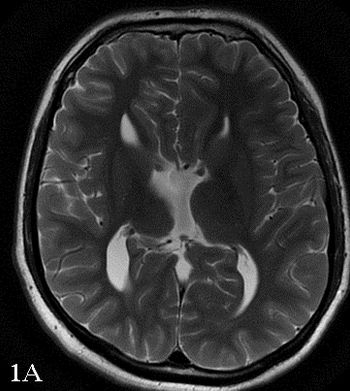

48-year-old female presented with complaint of seizures.

30-year-old male presented with nonspecific headaches.